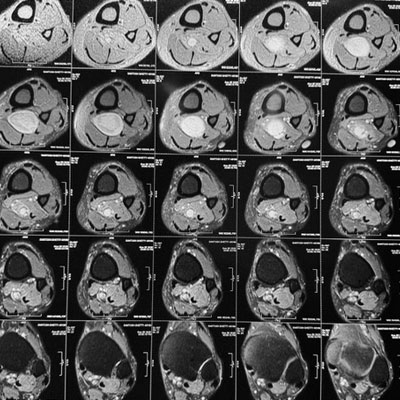

Dr. Ujwal Yeole is an experienced neurosurgeon specializes in treating a wide spectrum of neurological conditions including neuro-oncology, peripheral nerve disorders, vascular disorders, spinal pathologies, pediatric neurosurgery, neuro-trauma and skull base neuroendoscopic procedures.